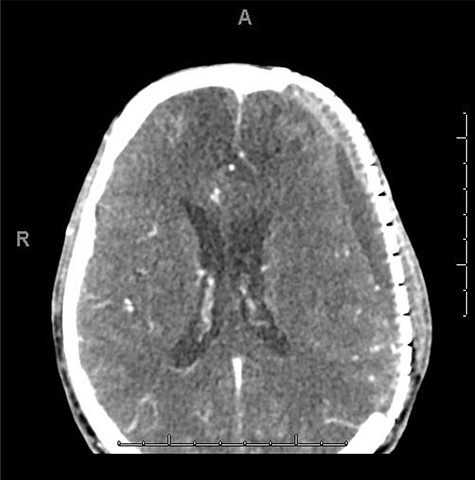

A 59-year-old male was found in the street with a head laceration. He was brought to the trauma bay as a pedestrian struck trauma patient with a prehospital GCS of 3. On arrival, his GCS was 11 (E3, V2, M6). An expanding neck hematoma was seen on exam. CT scan revealed scattered bilateral frontal contusions with hemorrhage in right basal ganglia, small bilateral acute SDH without significant mass effect, minimally displaced right temporal/occipital skull fracture and right-sided rib fractures 1–7 (flail chest) with hemopneumothorax (Fig. 1).

He was paralyzed, intubated and taken emergently to the OR due to nonresponsive hypovolemic shock. A right frontal ICP monitor was placed in the operating room while he was undergoing an emergency thoracotomy. Intraoperative ICP was in the 40s, and thus the patient was taken directly from the operating room to CT scan which showed enlargement of bilateral contusions, left greater than right, for which he was taken emergently to the operating room for a left hemicraniectomy (Figs 2 and 3).

CT head post thoracotomy with expansion of contusion with shift.